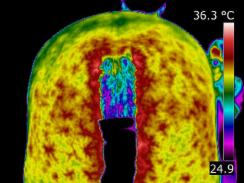

I offer trainers, riders and owners the benefit of monitoring their horses for injury and trauma during training and performance. Infrared imaging will safely and quickly identify areas of interest enabling you to adjust the training regime to reduce stress and help prevent injury. There is an increase in horses being monitored during training in this way. | |

As a form of “preventative medicine”, thermography has proven to be extremely valuable. After an Initial Scan which acts as our baseline data, we can compare periodic images. These regular thermal imaging scans can show up changes and irregularities that may be addressed and rectified, by management or treatment, before any actual damage has taken place. | |

Thermography also can predict and monitor joint inflammation. Normally cool joints might change their thermal pattern before the onset of lameness. The damaged joint can be detected due to the thermal pattern. The practitioner can then use thermography to monitor the effect of treatments. |